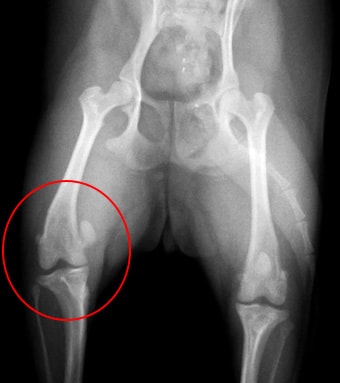

![]() 膝蓋骨脱臼を起こしているレントゲン写真  |

膝蓋骨脱臼

膝蓋骨とは膝のお皿の事で、このお皿の骨が脱臼することを膝蓋骨脱臼といいます。

チワワやトイプードル、ミニチュアダックスフンドなどの小型犬種に多く発症し、

主に内側へ脱臼します。膝蓋骨脱臼には重症度の分類がなされており、グレード1からグレード4まで様々あります。高グレードの膝蓋骨脱臼では痛みを伴い、また、脛骨変形や半月板損傷、膝関節炎が起こり、跛行の原因となります。